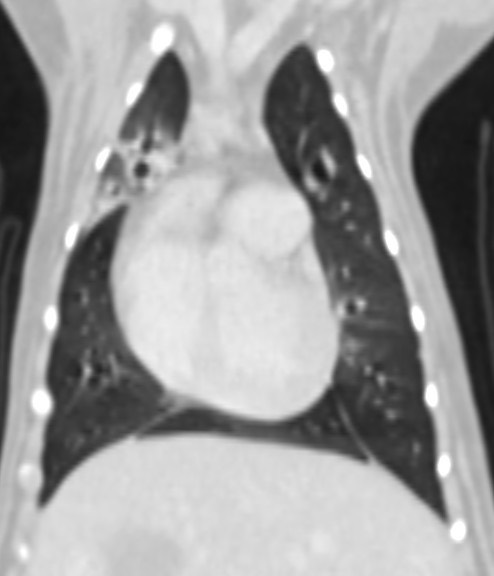

慢性咳嗽 支氣管肺炎 綠膿桿菌

電腦斷層掃描 氣管支氣管內視鏡探查 支氣管肺泡灌洗(broncho-alveolar lavage, BAL) 細菌培養

長達5個月的慢性咳嗽就診 反覆支氣管肺炎的狗狗Ainy,因為對藥物的反應時好時壞,

建議用電腦斷層掃瞄與氣管支氣管內視鏡探查評估病因與治療方式

電腦斷層檢查排除結構上異常引起的發炎,支氣管鏡探查發現病灶處有多量異常黏液樣分泌物,

於是進行支氣管肺泡灌洗(broncho-alveolar lavage, BAL)取得檢體,染色下細胞抹片可見發炎細胞跟桿菌,細菌培養結果為綠膿桿菌,對一般抗生素無效。

於是使用有效的抗生素治療6周後,追蹤到現在近半年都穩定囉